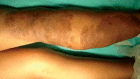

Plexiform neurofibromas are benign tumors originating from peripheral nerve sheaths, generally associated with Neurofibromatosis Type 1 (NF1). They are diffuse, painful and sometimes locally invasive, generating cosmetic problems. This report discusses an adolescent patient who presented with an isolated, giant plexiform neurofibroma on her leg that was confused with a vascular lesion due to its clinical aspects. Once the diagnosis was confirmed by surgical biopsy, excision of the lesion was performed with improvement of the symptoms.